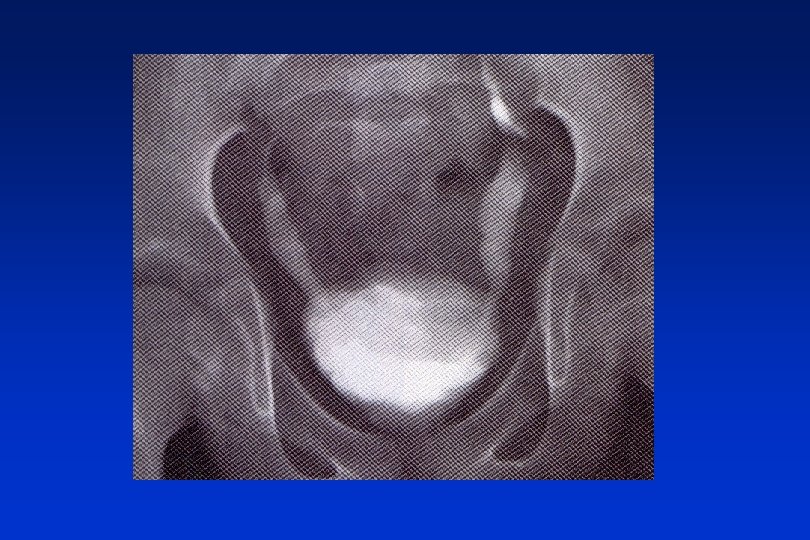

Echinococcus granulosus – liver cysts (man)

Echinococcosis E. granulosus

Echinococcus granulosus (dog)